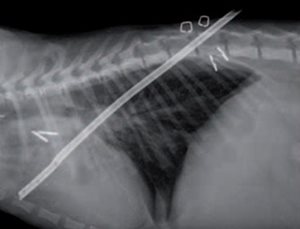

Cette intervention est de plus en plus réalisée sans thoracotomie, par thoracoscopie. La vidéo-chirurgie est bien adaptée à la réalisation d’une fenêtre péricardique permettant le drainage thoracique du liquide d’épanchement. Dans ce cas, la résection n’a pas besoin, comme en chirurgie conventionnelle, d’être subtotale, l’ablation d’une fenêtre de 5 cm suffisant [6,7] (photo 6).

Photo 6. Résection d’une fenêtre péricardique en thoracoscopie.